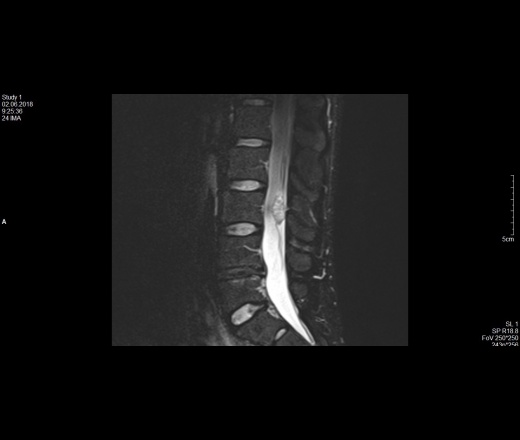

Образование в ветвях конского хвоста на уровне L3

32 года пол мужской. Жалоб на боли нет.

• МРТ с контрастом

Эпендимома терминальной нити? Или другая какая её опухоль.

Есть ли вариант, что это не злокачественное образование?

Доброкачественное и злокачественное - понятие относительное. Можно подождать полгода и сравнить размеры. Или удалить сейчас, не дожидаясь компрессии корешков и их атрофии.